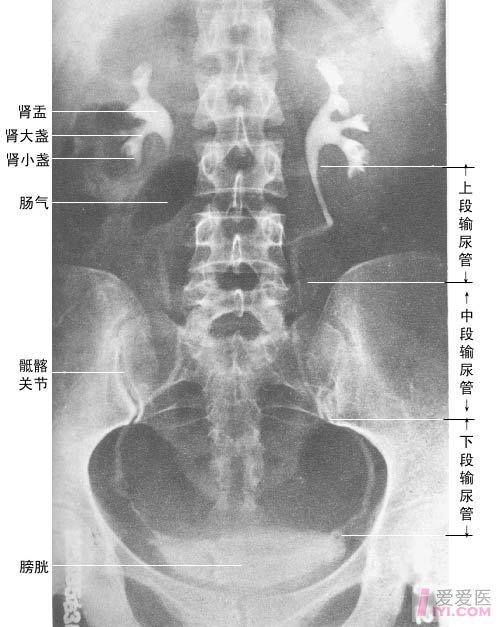

正常腹部平片图

正常腹部平片图,腹部图片位置图